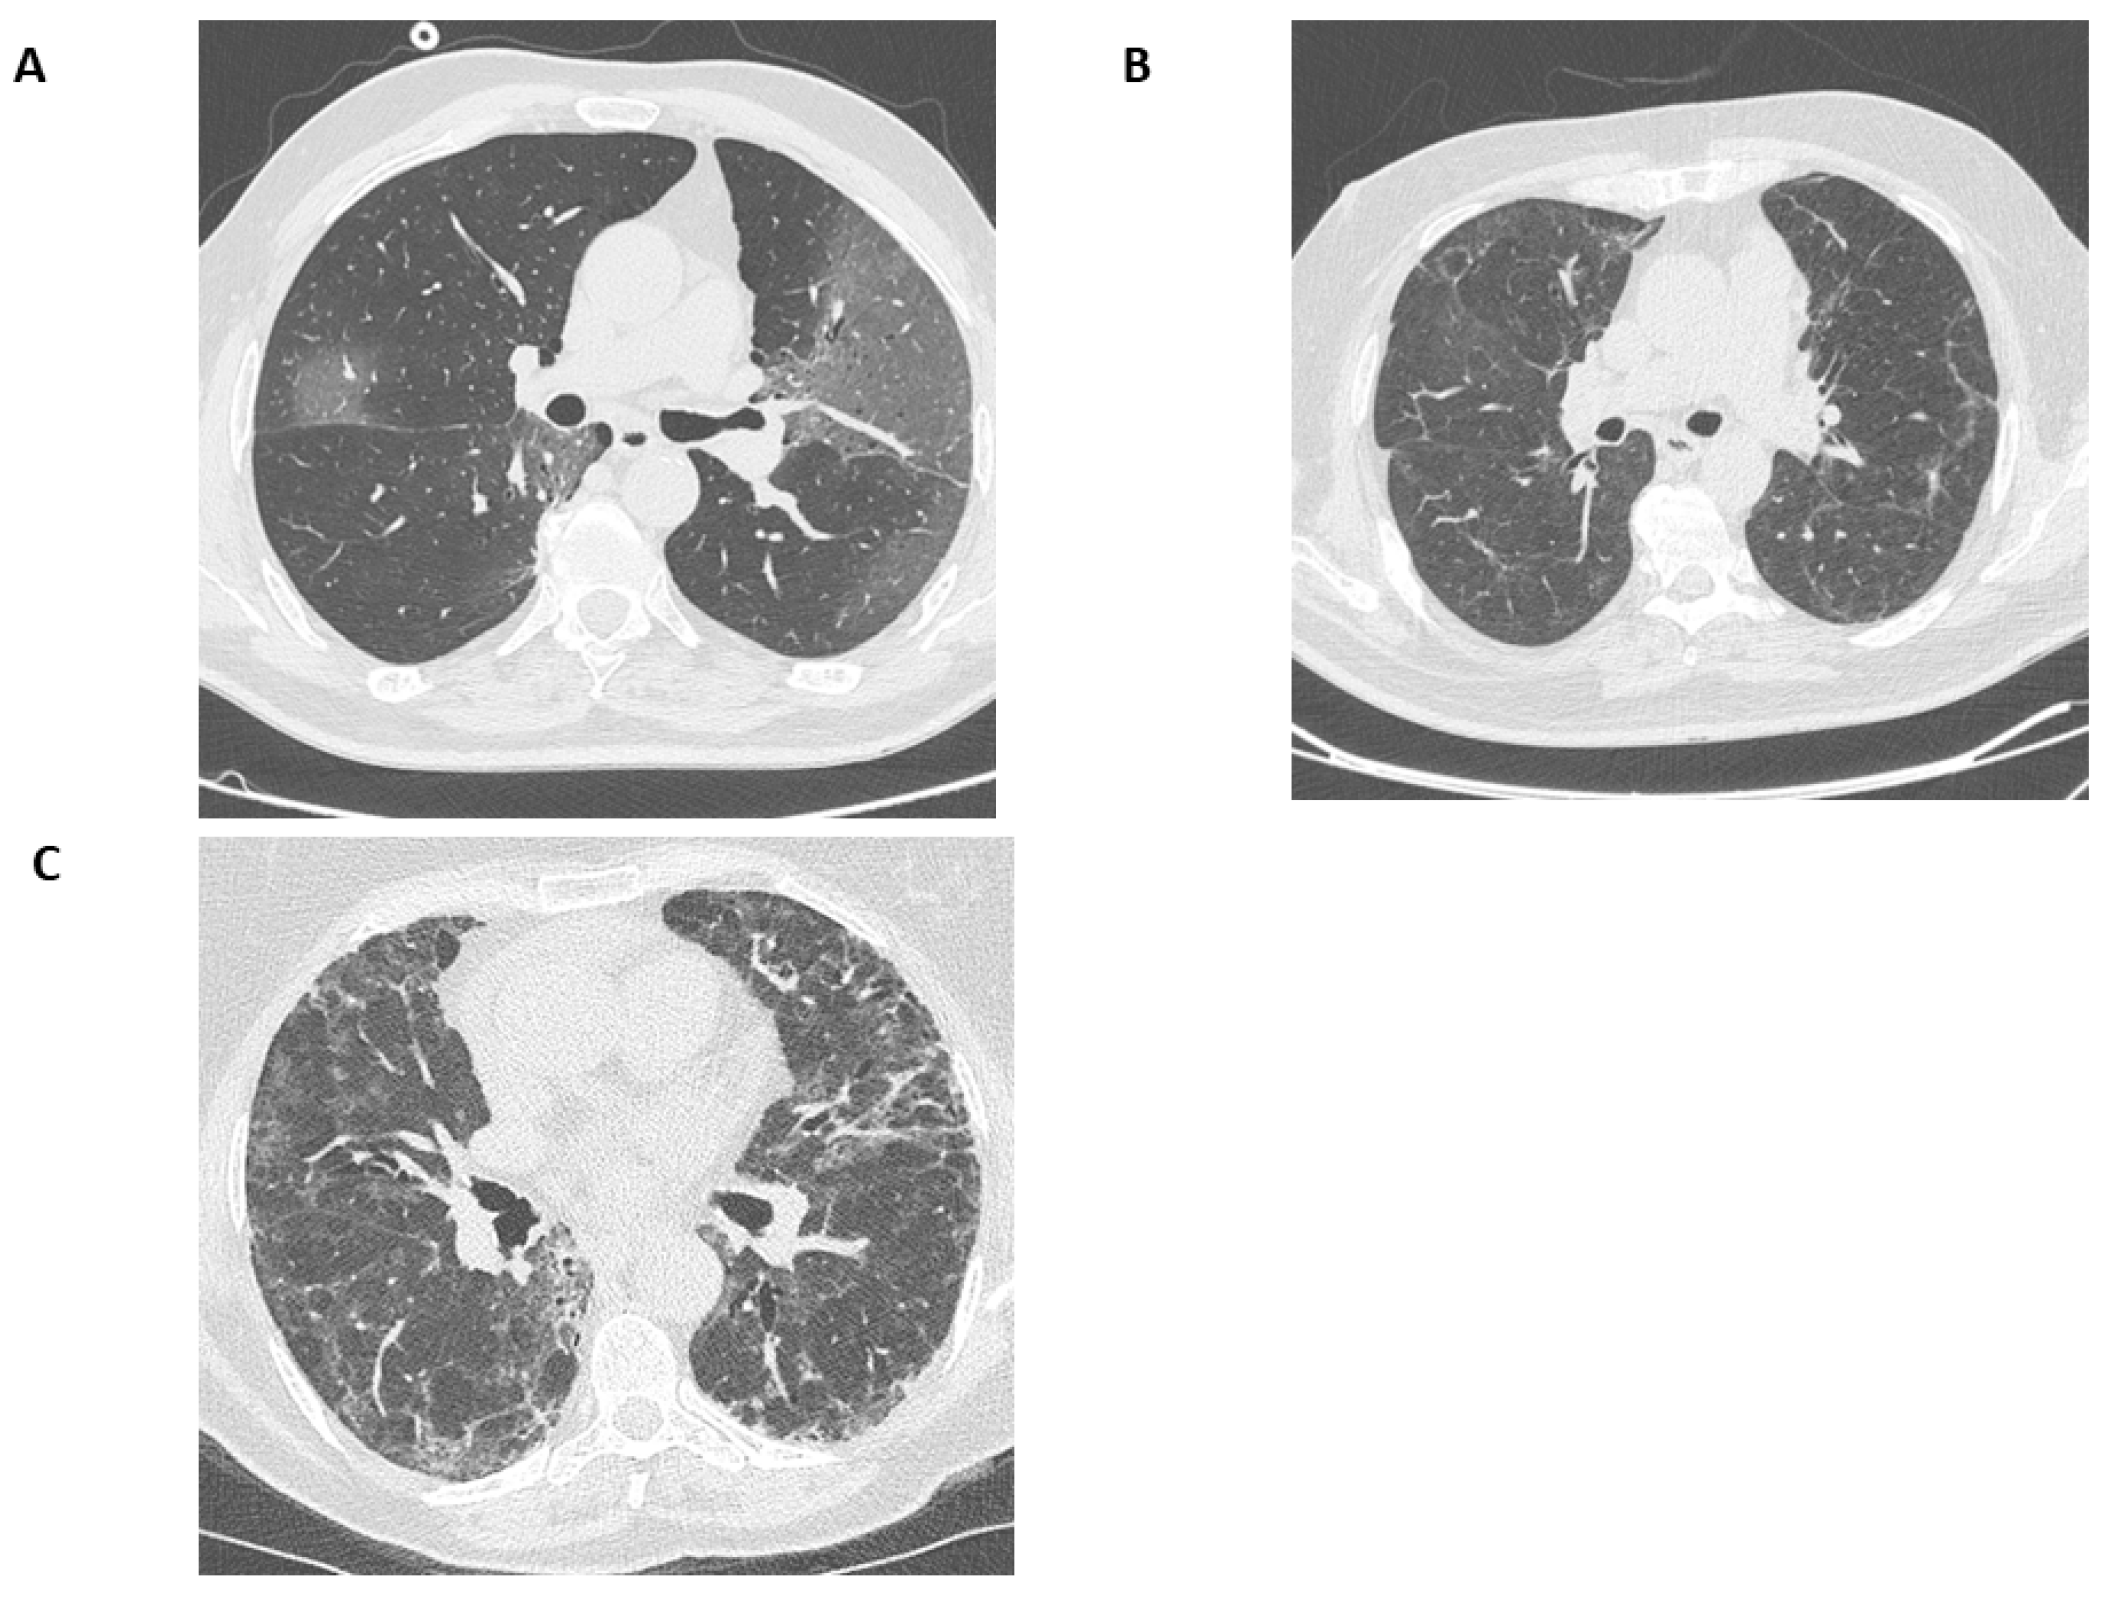

3.3. CT Findings